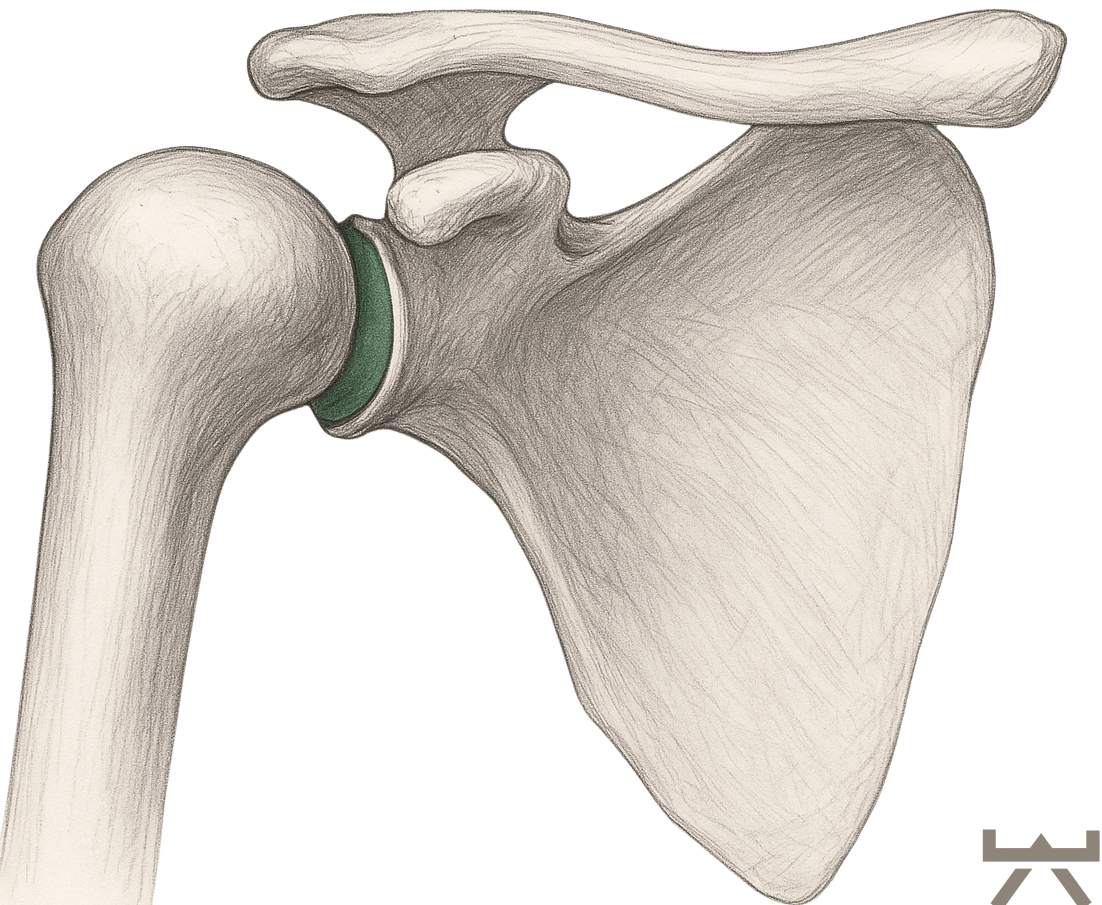

ANATOMIE

Die Schulter ist geschickt zusammengesetzt. Es ist ein Komplex aus nicht weniger als 4 Gelenken, nämlich:

- Das Glenohumeralgelenk. Dies ist die Verbindung zwischen Oberarm und Schulterblatt. Kopf und Pfanne sind durch die Schulterkapsel, auch Rotatorenmanschette genannt, verbunden. Kleine Muskeln, die extrem wichtig sind, um den Schulterkopf in der Pfanne zu halten.

Verglichen mit der tiefen knöchernen Hüftpfanne ist die Schulterpfanne eher als kleine Schale zu bezeichnen. Diese Schale wird durch das Labrum noch verstärkt. Das Labrum ist einen Knorpelring, der direkt an der Gelenkpfanne der Schulter ansetzt. Das Labrum ist wiederum mit den Muskeln der Rotatorenmanschette verbunden, die zusammen die Schulterkapsel bilden. Sie sollten diese Muskeln als eine dynamische Gelenkpfanne betrachten, die zur Stabilisierung des Schulterkopfes beiträgt, indem sie genau im richtigen Moment angespannt wird, wenn sie ihre Bewegungen ausführen.

Für die Anforderungen, die wir an die Schulter stellen, ist ihre Anatomie sehr sinnvoll. Die minimale Gelenkpfanne ermöglicht es uns, den Arm frei in allen Richtungen zu bewegen. Durch diese Bewegungsfreiheit wird die Stabilisierung der Schulter für den Körper jedoch schwieriger.

Wie sie bei Absatz „Anatomie“ mitbekommen haben, ist die Schulter von allen Gelenken im menschlichen Körper, bei weitem das Gelenk, dass am häufigsten auskugelt. Dies ist nicht verwunderlich, wenn man die Größe der Schulterpfanne vergleicht mit dem Schulterkopf.

Da die Gelenkkongruenz (die Deckungsgleichheit oder Kontaktfläche des Gelenks) also minimal ist, muss die Stabilität des Gelenks, vor allem von unserer Muskulatur, kompensiert werden.